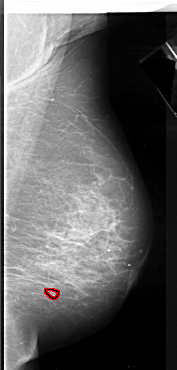

A_1085_1.RIGHT_CC

RIGHT_CC LINES 5581 PIXELS_PER_LINE 2806 BITS_PER_PIXEL 16 RESOLUTION 42 OVERLAY

FILE: A_1085_1.RIGHT_MLO.OVERLAY

TOTAL_ABNORMALITIES 1

ABNORMALITY 1

LESION_TYPE CALCIFICATION TYPE ROUND_AND_REGULAR DISTRIBUTION CLUSTERED

ASSESSMENT 4

SUBTLETY 4

PATHOLOGY MALIGNANT

TOTAL_OUTLINES 1

BOUNDARY